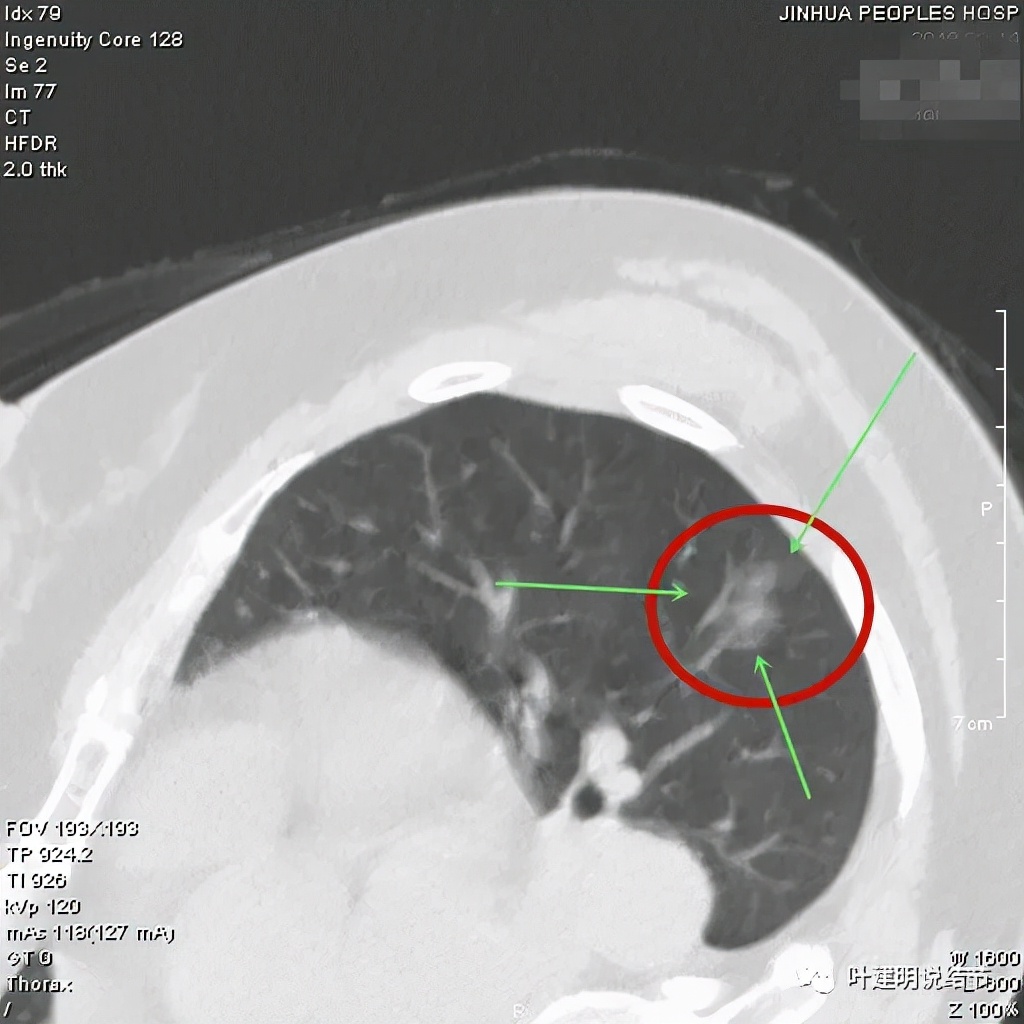

这样的病灶需要手术吗?经过手术确诊,分别是不典型增生、原位腺癌、微浸润性腺癌与浸润性腺癌。术前我们怎么能够来区分谁是原位癌,谁是浸润性腺癌,谁该开而谁又不需要开?再如下面这几例:

它们都是需要手术的,因为都是混合磨玻璃结节,而且影像符合浸润性腺癌的影像表现,但术后病理却分别是:慢性炎伴非典型增生、原位腺癌、微浸润性腺癌以及浸润性腺癌。同样,我们单从影像无法来区别到底是什么病理类型。即使大部分时候能准确判断,但临床上不断会有判断不对的病例出现。而肺磨玻璃结节目前最主要的诊断手段仍是胸部CT检查,细针穿刺活检因组织标本量有限或病灶小、位置深同样无法百分之百能准确,还有并发症或种植转移之虞。而影像的判断即使我们不断总结分析、回顾研究,仍难确保病理类型的术前判断精准。那么,把原位腺癌剔除出肺癌的范畴,而仍无法在术前确诊的情况下,效果与意义大打折扣!因为我们无法排除它是浸润性腺癌的可能性!对于肺磨玻璃结节,影像上若更符合微浸润或浸润性腺癌,经过随访或适当的处理后仍存在而无吸收好转,手术肯定得做,切出来是慢性炎也好、是非典型增生或原位癌也好,都是合理的,也是值得的,尤其是楔形切除的话。我们如果按我之前一直呼吁的,不要执着于术前判断具体的病理类型,而是依风险高低来评判,就会更加符合临床,也更合理决定手术干预与否。比如纯磨玻璃结节,稳定、密度低,随访无进展或进展缓慢的,定义为低风险结节,可以随访,那么就可避免许多肺结节过早手术;而如今天分享的这例,虽然术后病理是原位腺癌,理论上可以观察随访的,但因影像上是混合磨玻璃结节,有微血管征,有毛刺征,有密度杂乱,且随访后无吸收好转,就是中高风险的,则仍宜手术切除。